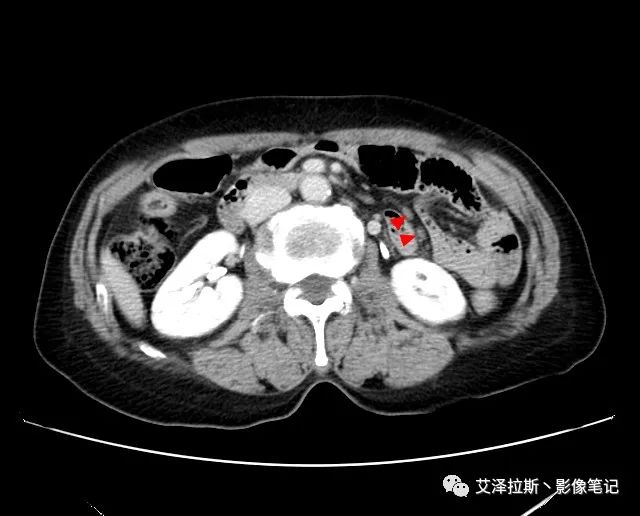

以下為累及的區(qū)域淋巴結(jié),共計15個區(qū)域:

【影像所見】 胃竇部狹窄,胃壁環(huán)形增厚,小彎側(cè)見一巨大潰瘍,周圍伴“環(huán)堤征”,漿膜面不完整,胃周脂肪見網(wǎng)格狀條索影,病灶與肝臟左葉、胰腺鉤突脂肪間隙消失,增強(qiáng)掃描病灶明顯強(qiáng)化。引流區(qū)內(nèi)約15個區(qū)域淋巴結(jié)受累。

【診斷意見】 胃竇部胃癌(T4N3期) 該病例腫塊突破漿膜層,與肝臟左葉、胰腺鉤突分界不清,脂肪界面消失,定為T4期; 受累及的淋巴結(jié)為15個區(qū)域,定為N3; 有無遠(yuǎn)處轉(zhuǎn)移尚不明確,所以M期暫時無法確定。